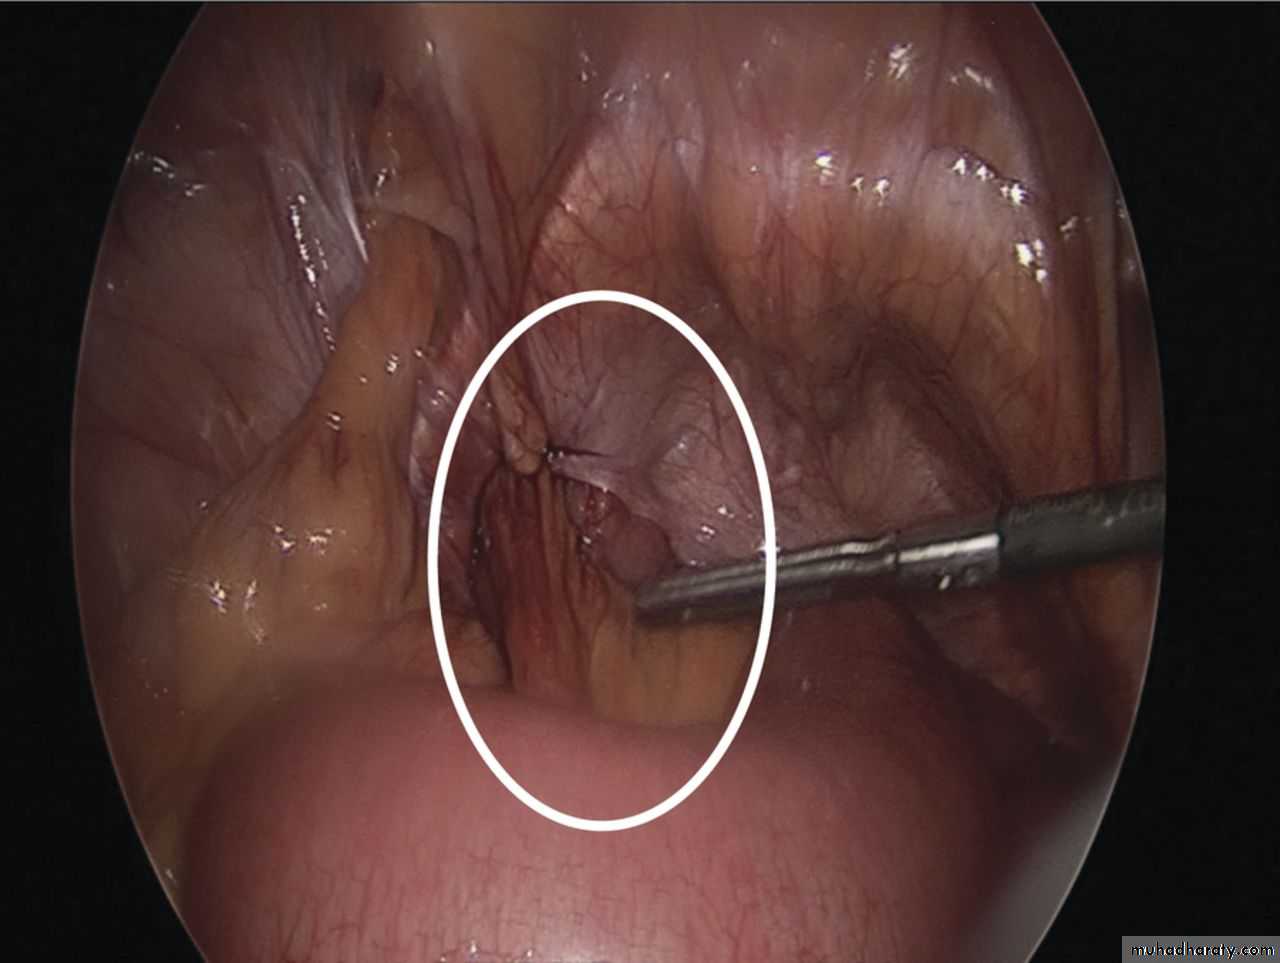

Intraoperative image showing left sided obturator hernia within white outline and incidental femoral hernia at 11’o clock position.

Noel P. Lynch et al. J. surg. case rep. 2013;2013:rjt050